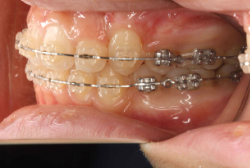

凸凹な歯並びのことを叢生といいます。矯正歯科に来院する患者様の主訴の中で、最も多いのが「配列の凸凹を真っ直ぐにしたい」というものです。歯の大きさと顎の大きさの調和がとれていないことが原因です。

凸凹を主体としたケースの場合、当院の平均治療期間は18ヶ月ですので、このケースは少し長めに経過しました。理由の一つは凸凹の程度がかなり重症だったと言うことですが、もう一つは、右下第2大臼歯が45度くらい前傾していたため、それを整直化させるために時間を要したと考えています。いずれにしても最終結果は大変よい状態と思います。

治療前は並びが乱れて見た目が悪いというのはもちろん問題ですが、歯科医学的に一番困るのは噛み合わせが悪いという点です。上下の犬歯(3番目の歯)は、上下的に離れた位置にあるため接触することができません。つまり歯としては存在していても、歯としては機能していないということです。

凸凹の強弱とは関係なく装置を最初に付けて数日は強い不快感・疼痛がありますが、数日~2週間で慣れてきます。特にこの症例のように凸凹が厳しい場合は、凸凹の歯の表面にさらに凸凹した装置が付きますので、非常に歯が磨きにくくなり虫歯や歯周病のリスクが高まりますので、歯磨き指導を十分に受けて、セルフメンテナンスに努めることが重要です。

本症例のように前歯部の凸凹が強い場合、歯間部歯肉が痩せて退縮する場合があります(ブラックトライアングル)。またマルチブラケット法全般に言えることは、口腔粘膜の違和感、金属アレルギー、歯根吸収などのリスクがありますので、事前に担当医より詳しい説明を受けて下さい。